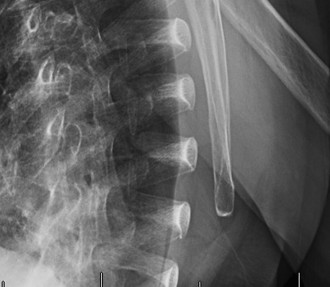

Understand the operative treatment of SC joint osteoarthritis and the important structures to preserve? CASE 29 Dr. Robert J. Stewart A 57-year-old, right-hand-dominant female presents with left shoulder pain and stiffness for the last 3 months. She has a history of diabetes, hypothyroidism, and breast cancer. She reports having difficulty sleeping on her left side. She localizes her pain over the deltoid insertion. The stiffness has become worse. The pain has been improving over the last 3 weeks but is exacerbated by extreme left shoulder motion. She is having difficulty dressing and combing her hair. She works as a statistical analyst and sits at a desk most of the day. On physical examination, she has normal strength with left shoulder abduction and external rotation, a negative cross-body adduction test, and no pain with a supinated O’Brien’s test. An x-ray is obtained and shown in Figure 2–76.

Figure 2–76

The correct answer is (D). Adhesive capsulitis (AC) is a specific pathologic entity that produces subsynovial chronic inflammation resulting in capsular thickening, fibrosis, and adherence of the capsule to itself and the anatomic neck of the humerus. The thickened and stiff capsule causes pain and a restraint to motion. This is called primary, or idiopathic, AC. The remaining answer choices are incorrect and can result in symptoms similar to those of AC (i.e., loss of shoulder motion and pain), but their underlying etiology is different. It is important to recognize that all these conditions can cause a stiff and painful shoulder (a “frozen shoulder”) but is not necessarily AC. AC occurs more frequently in sedentary females in the non-dominant hand, and has been associated with diabetes mellitus, thyroid dysfunction, breast cancer treatment, cardiovascular disease and cerebrovascular disease.

The patient is diagnosed with stage 3 adhesive capsulitis. On physical

examination, which of the following is the most likely to be found?

The correct answer is (A). A “frozen shoulder” results from a known intrinsic, extrinsic, or systemic cause that may result in a global or partial loss of shoulder motion. However, adhesive capsulitis (AC) is idiopathic and always results in a global loss of passive and active range of motion. Answer B would likely result from a known cause, such as an excessively tight anterior soft-tissue repair for instability. Answers C, D, and E are all associated with pain during motion. This would be expected in the early stages of AC, but due to patient’s reported decreasing pain, these answer choices can be eliminated. Table 2–11 lists the stages of AC. The diagnosis and staging is made clinically. The table provides a description of the arthroscopic and histopathologic appearances. An intra-articular anesthetic injection can be used to distinguish stages 1 and 2.